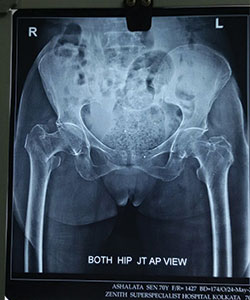

Case 1: Hip Fracture (Intertrochanteric Fracture)

70 Years female presented with right hip fracture following a fall in the bathroom

XRAY - 1

X-RAY showing right hip fracture (Intertrochanteric Fracture)/p>